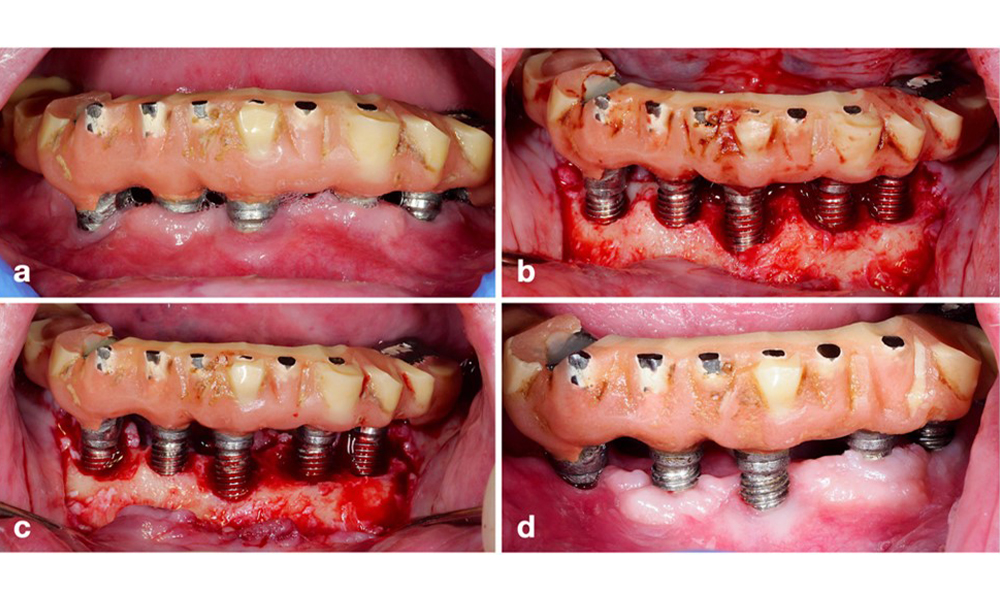

Defect extent, implant position, and its strategic importance determine whether an implant can or should be treated. Similar to a non-treatable (hopeless) implant, a severely affected implant in a multiple-unit restoration may be irrelevant for treatment, as its loss does not compromise the prosthetic restoration. Consequently, it is advisable to consider explantation either upon diagnosis or during surgical intervention (figure 8).

The prosthetic restoration should be removed during both non-surgical and surgical treatment to improve access to the implant surface. The choice of surgical intervention (e.g., resective, reconstructive, or combined) depends on several factors: (1) defect morphology (e.g., horizontal, dehiscence, intra-osseous, or combined) (figure 10), (2) implant surface (i.e., turned or modified/”rough”), and (3) presence or absence of sufficient keratinised and attached mucosa.